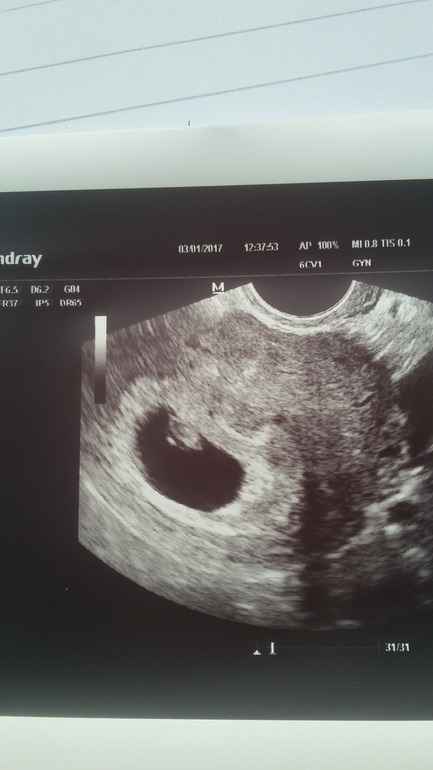

Узи 5 нед 4 дня

Вот почему нельзя ходить на узи раньше 7 недель. 5+6 ПЯ в матке, есть жм, эмбриона четко не видно, сердца тем более. Все хорошо,малышке 3 месяца.

это 5+3